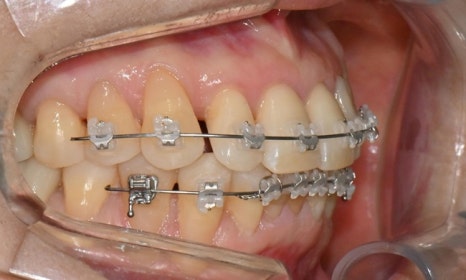

치료 2개월 후

치료 2개월 후 환자분께서 가장 고치고 싶어하셨던 오른쪽 앞니가 벌써 배열이 가지런하게 변한 것을 확인할 수 있습니다.